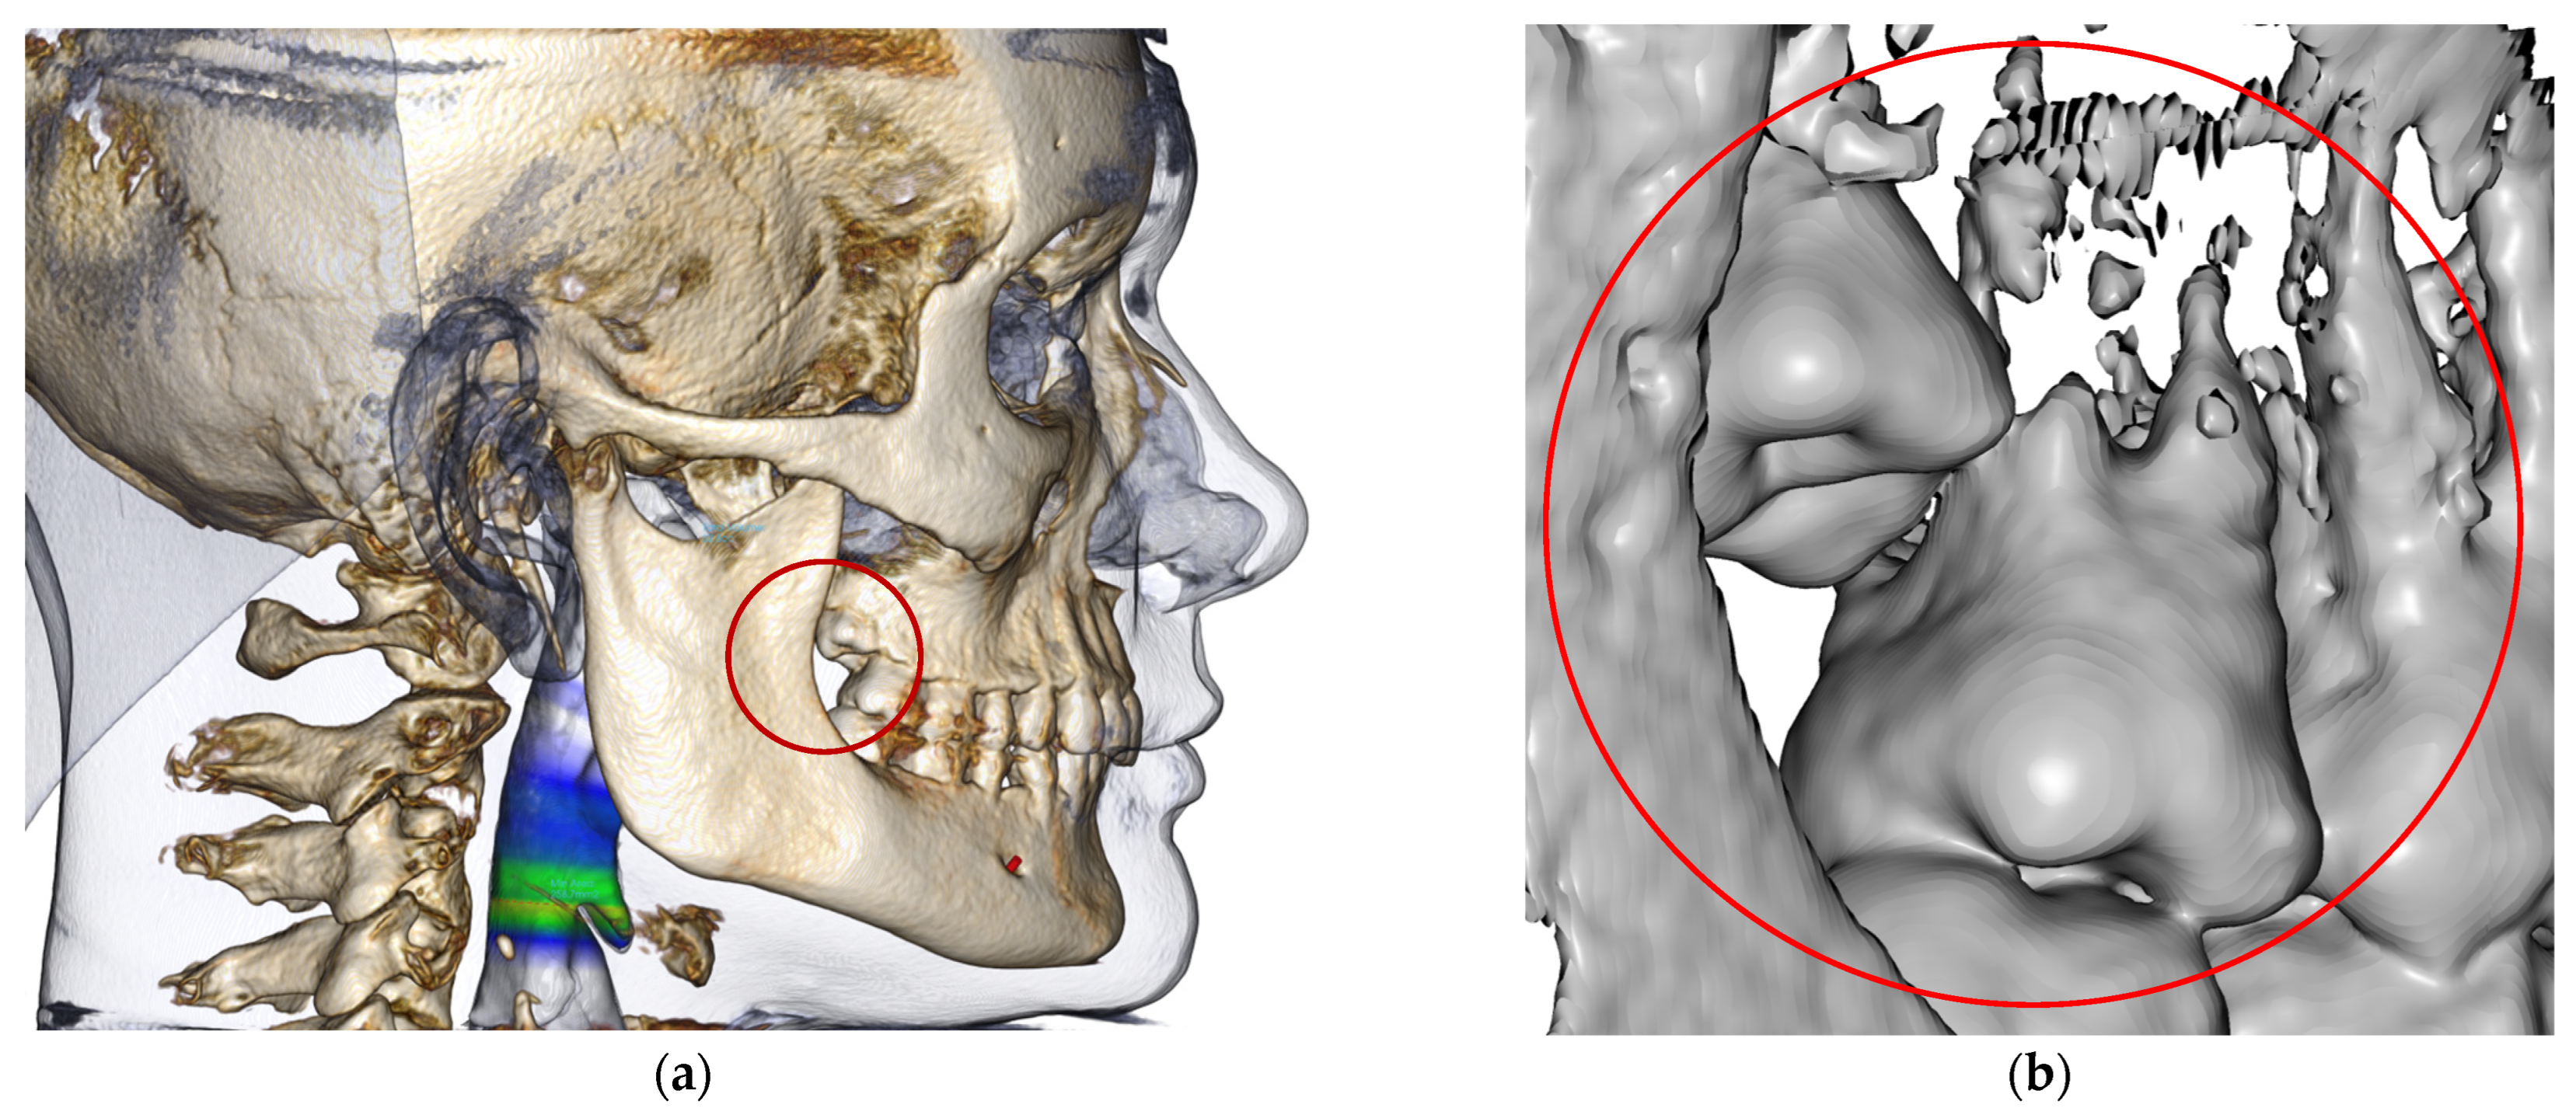

- Diagnocat (USA—Diagnocat LTD, Miami, FL, USA) for AI segmentation;

- Invivo 7.0 (Anatomage, Santa Clara, CA, USA) for segmented model analysis;

2.3. Processing CBCT